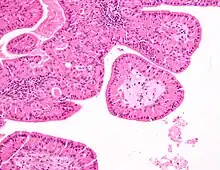

The appearance of this tumor under the microscope is unique. There are cystic spaces surrounded by two uniform rows of epithelial cells with centrally placed pyknotic nuclei. The cystic spaces have epithelium referred to as papillary infoldings that protrude into them. Additionally, the epithelium has lymphoid stroma with germinal center formation.